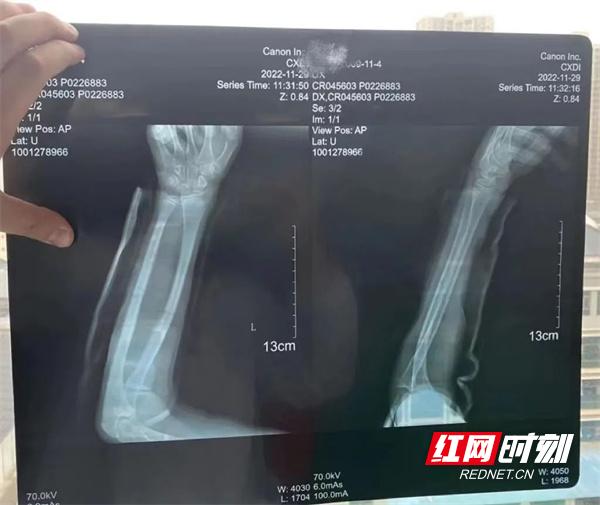

入院时左侧尺桡骨X片。

前段时间,十三岁的小康(化名)在学校玩耍时不慎摔倒,当时就感觉到左前臂及肘部肿痛难忍,而且腕关节部分活动受限。家人带着小康在当地的医院就诊,拍片检查后显示小康是“左侧尺桡骨中段骨折”,当地医院建议小康的家人前往郴州市中医医院接受治疗。

手法复位一周复查X片。

固定后经X光复查,可以看到各断端对线对位严丝合缝。袁医生嘱咐小康的家长要注意手部皮肤颜色,观察末梢血液循环有无出现障碍,并要每天进行握拳练习。之后配合局部外敷中药、口服中药活血化瘀消肿止痛等疗法,并配合以科学合理的康复治疗,一周后拍片复查显示小康的左手手臂恢复状况良好。